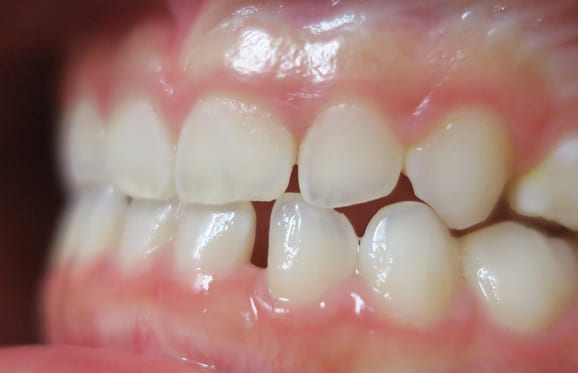

● 歯根が折れ保存不可の歯を抜歯して、そのスペースに八重歯を並べた症例

藤沢デンタルオフィスの虫歯や破折で抜歯後の部分矯正